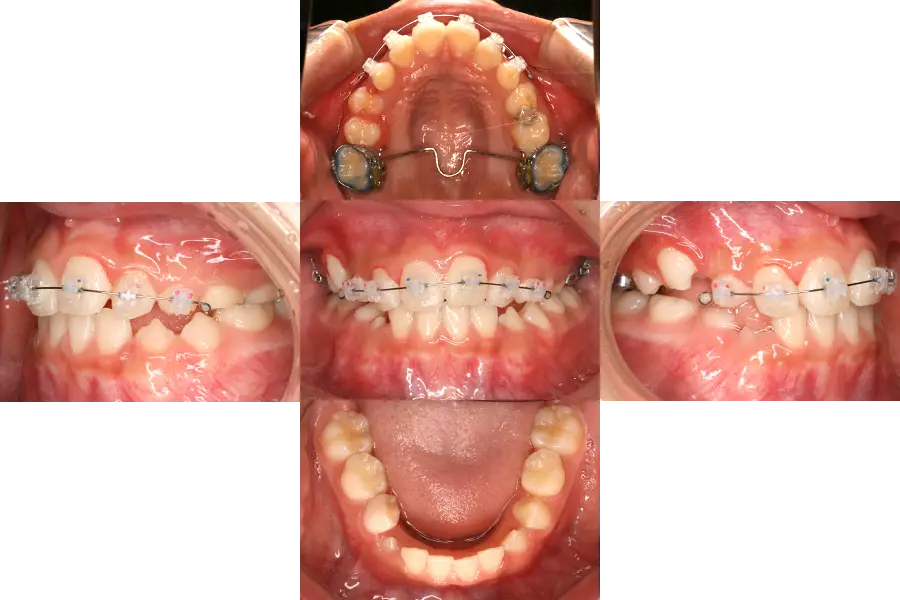

反対咬合の小児矯正治療例

- 主訴

- 反対咬合

- 治療開始年齢

- 9歳

- 診断

- 下顎前突、反対咬合、過蓋咬合

- 難易度

- 重度

- 使用した装置

- バイトブロック、唇側ブラケット装置、歯列矯正用咬合誘導装置(ムーシールド)

- 治療期間

- 約1.0〜1.5年

- 費用(税込)

-

基本料金 399,300円 調整料(約12〜18回) 来院ごと6,600円 総額 478,500円~

- 治療について

初診時は、下顎前突と過蓋咬合、前歯部での早期接触による顎のズレが認められました。

下顎を前方に出さなくとも、顎が自然の位置で咬めるよう、歯にバイトブロックを装着しながら、前歯部にブラケット装置を付け、早期接触および反対咬合を改善しました。

1期治療終了後、永久歯の生え変わりと顎の成長の変化を観察していたところ、成長期に入り、下顎の急激な成長が認められたため、就寝時に歯列矯正用咬合誘導装置(ムーシールド)を装着してもらいながら、経過をみました。

成長変化がほぼなくなってきた段階(1期治療終了後3年経過時)において、良好な歯並び・咬合が得られています。もう少し成長変化がある可能性があるため、今後も成長観察が必要です。

- 治療のリスク

違和感、痛み、しゃべりにくさ、歯磨きの難しさ、虫歯のリスク増大、矯正装置の脱落、可撤式装置(ムーシールド)が使用できない可能性、顎の成長や歯・顎の大きさによっては2期治療で小臼歯等の抜歯が必要になる可能性、自費診療。